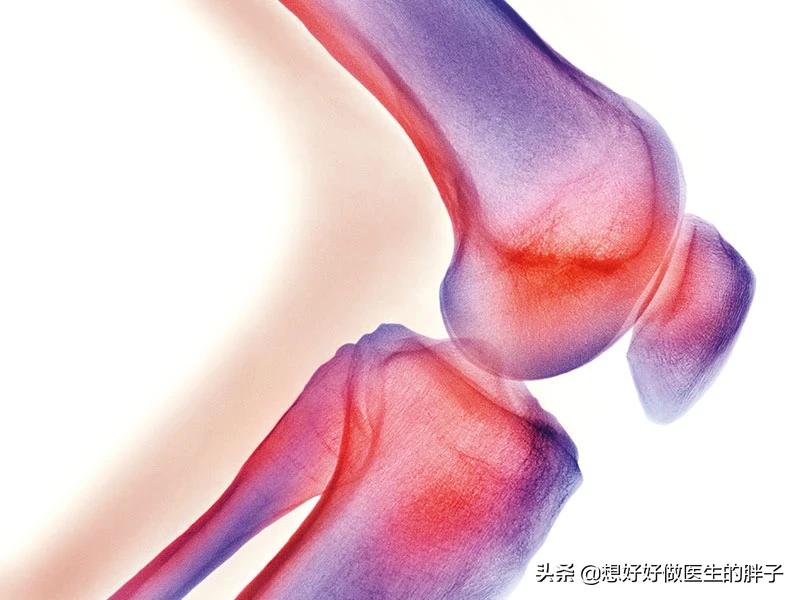

很多人的认识当中,我们的膝关节是一个关节,但在专业医生眼里,我们的膝关节是有两个股骨-胫骨间室以及髌骨-股骨间室三个关节共同构成的。而髌骨软骨软化主要是发生在髌骨-股骨间室这个关节。大家看下面这两个动图可以更好的理解在髌骨的活动轨迹以及特点,在关节屈伸过程当中,随着屈膝角度的加大,髌骨与后方的股骨接触会越来越紧密,压力也会越来越大,另外在正常屈伸关节的时候,髌骨的活动轨迹不应该有倾斜的。

所谓的髌骨软骨软化可不是软骨变软了,而是软骨磨损了。导致髌骨软骨软磨损的原因有很多,比如长时间的过度使用,长时间的蹲着,长时间的反复做关节的扭转动作、髌骨先天发育异常以及体重、遗传等因素。大家可以想一想,如果长时间的蹲着,髌骨以及后方的股骨之间是一直在顶着的,这个压力始终持续的存在,非常容易导致软骨的磨损;另外如果因为某一些先天因素以及过度使用导致髌骨明显的向外侧倾斜,髌骨与其后方的股骨之间的压力也会越来越大,这也会造成软骨的磨损。